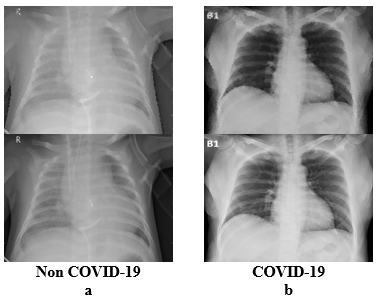

Figure 3 shows a sample of chest X-ray images of COVID-19 and non-COVID-19. Such type of images has been taken from the dataset used for the proposed model. Figure 3.a shows the chest X-ray images of Non-COVID-19 people, and Figure 3.b shows the chest X-ray images of COVID-19 infected people.

Figure 3. Sample Images of Non COVID-19 and COVID-19 patients [23-29]